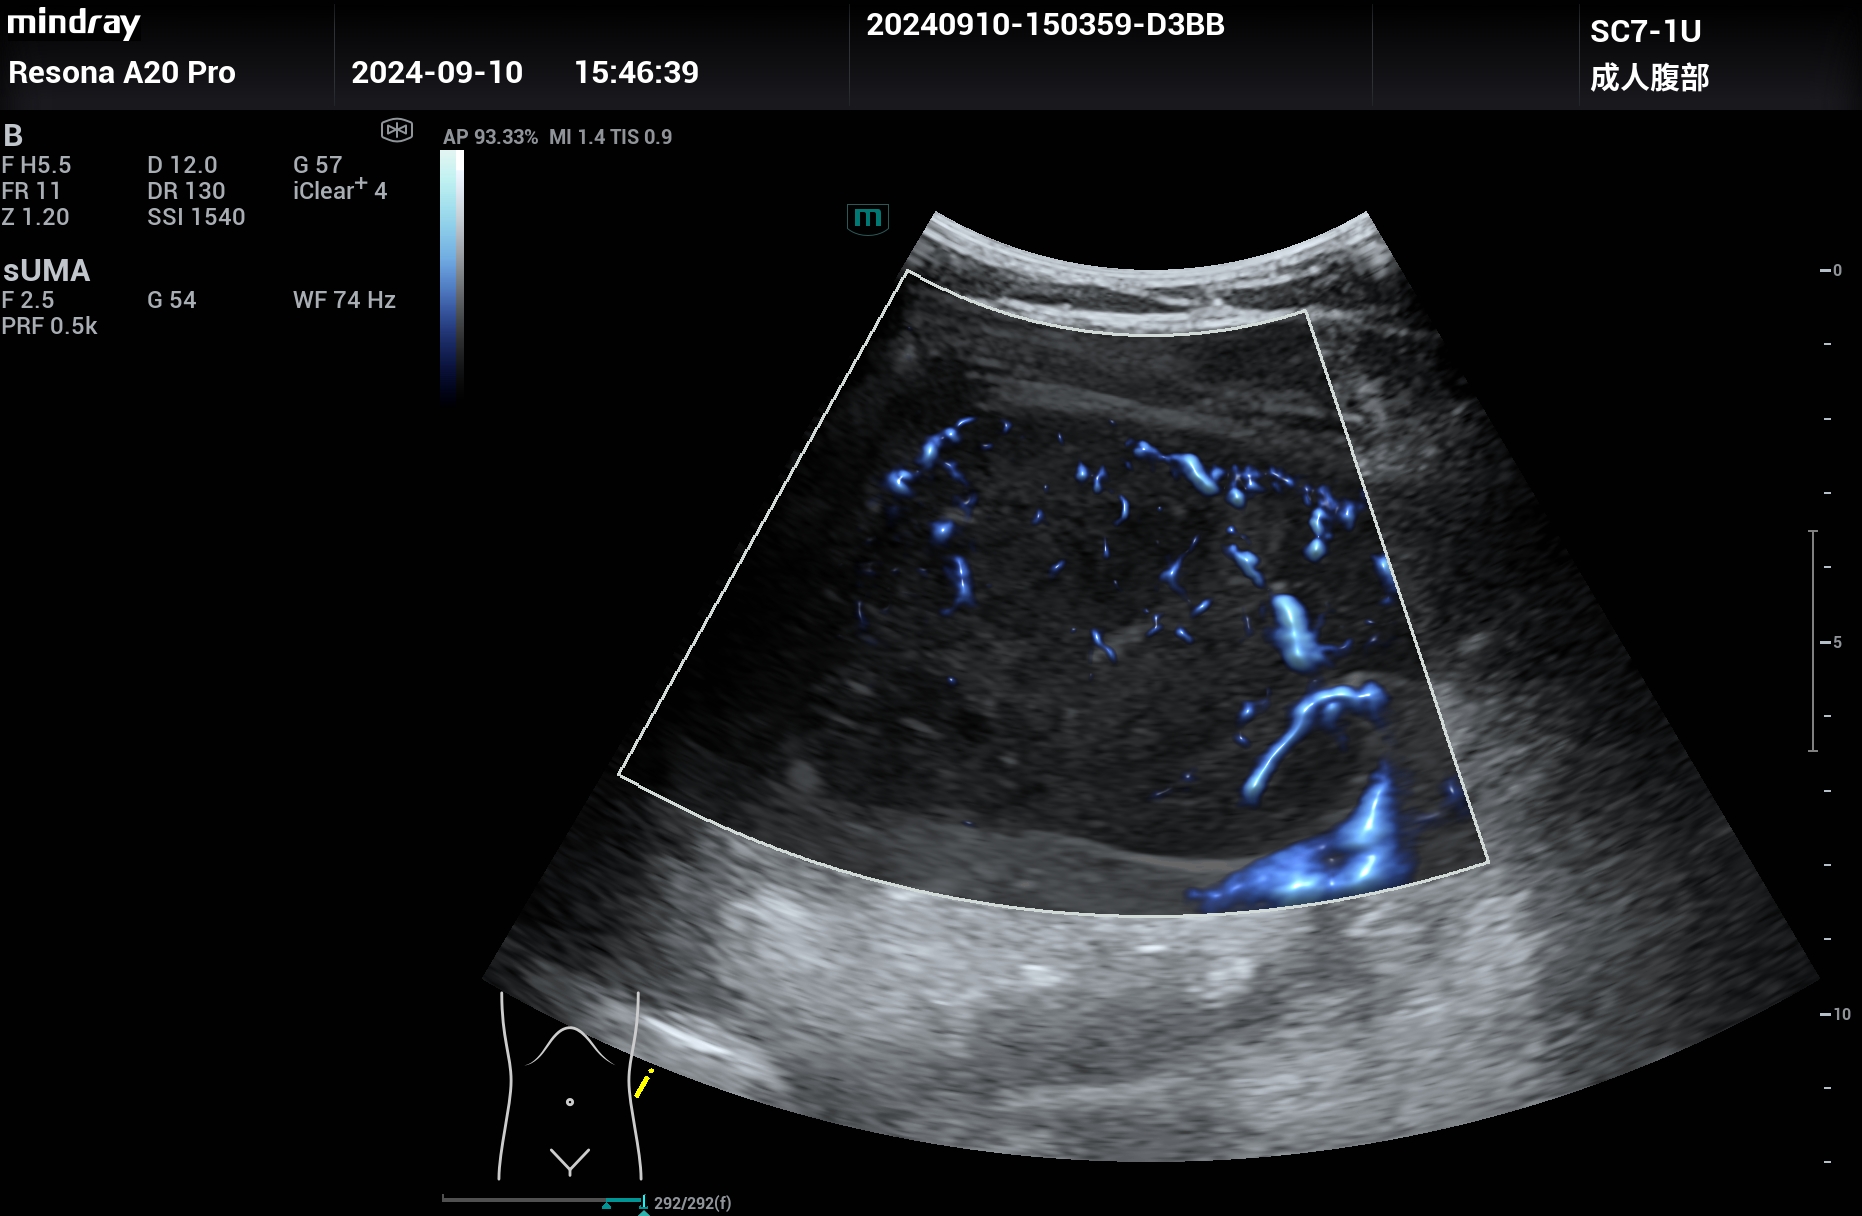

肾脏癌性大包块,扩展成像,腹部探头变成腔内探头的超宽视野,但分辨力依然清晰,超高端Resona A20

肾脏癌性大包块,腹部探头扩展成像,腹部探头成腔内探头的超宽视野,但分辨力依然清晰。